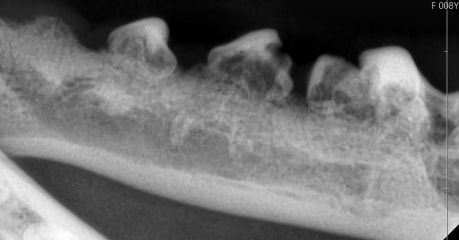

歯周病治療機器

歯周病治療の使用機器は歯垢や歯石を取り除く機器が中心になります。

歯石除去には歯に優しいマグネット式スケーラーを使用しています。縁下や細い溝にも対応可能です。